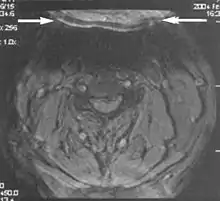

Metal artifacts occur at interfaces of tissues with different magnetic susceptibilities, which cause local magnetic fields to distort the external magnetic field. This distortion changes the precession frequency in the tissue leading to spatial mismapping of information. The degree of distortion depends on the type of metal (stainless steel having a greater distorting effect than titanium alloy), the type of interface (most striking effect at soft tissue-metal interfaces), pulse sequence and imaging parameters. Metal artifacts are caused by external ferromagnetics such as cobalt containing make-up, internal ferromagnetics such as surgical clips, spinal hardware and other orthopaedic devices, and in some cases, metallic objects swallowed by people with pica.[3] Manifestation of these artifacts is variable, including total signal loss, peripheral high signal and image distortion (Figs 3 and 4).[1] Reduction of these artifacts can be attempted by orientating the long axis of an implant or device parallel to the long axis of the external magnetic field, possible with mobile extremity imaging and an open magnet. Further methods used are choosing the appropriate frequency encoding direction, since metal artifacts are most pronounced in this direction, using smaller voxel sizes, fast imaging sequences, increased readout bandwidth and avoiding gradient-echo imaging when metal is present. A technique called MARS (metal artifact reduction sequence) applies an additional gradient, along the slice select gradient at the time the frequency encoding gradient is applied. ==Signal processing dependent artifacts== The ways in which the data are sampled, processed and mapped out on the image matrix manifest these artifacts.[1]